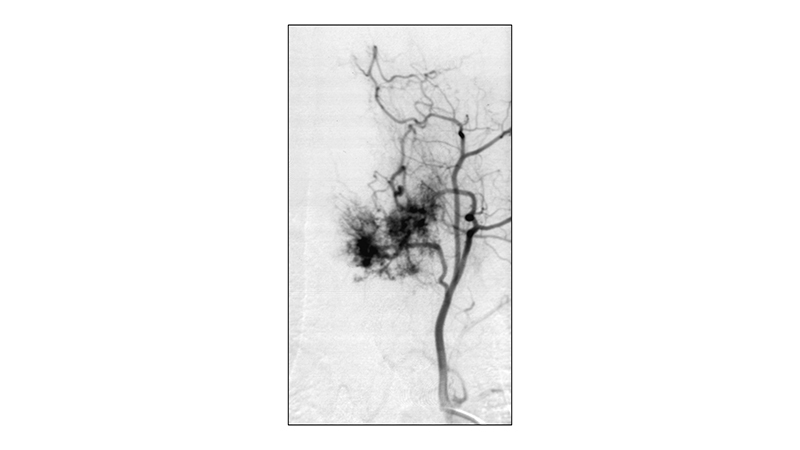

Εικόνα 3: Αγγειογραφία της αριστερής Θ3 μεσοπλευρίου αρτηρίας, σε προσθιοπίσθια προβολή, με άρδευση του κεντρικού και αριστερού πλαγίου τμήματος του όγκου.